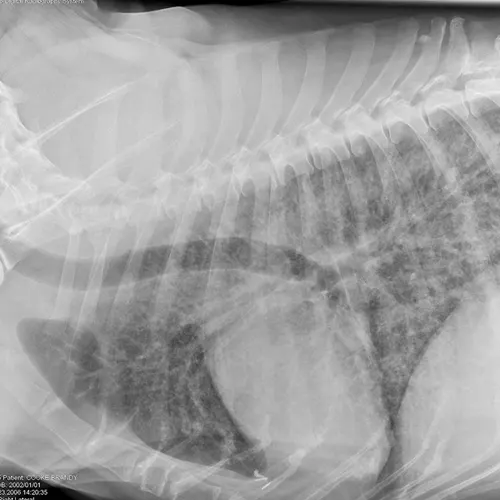

Dogs with bacterial pneumonia are typically presented with acute-onset coughing, lethargy, inappetence, and/or respiratory distress. An inflammatory leukogram and pyrexia, although common, are not always present. Radiographs may reveal an interstitial-to-alveolar pattern with a cranioventral distribution (Figure 1). Atypical distributions can also occur.5

FIGURE 1

(A) Bronchopneumonia. Cranioventral distribution of alveolar disease with air bronchograms. (B) A patchy distribution can be observed on the lateral projection. The changes overlying the heart may be missed in subtle cases.